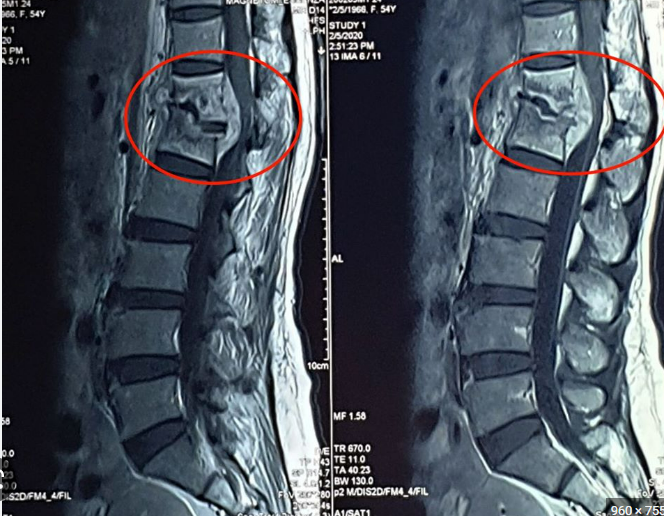

Lao cột sống chiếm khoảng ½ tổng số lao xương khớp. Đối với lao cột sống tổn thương vùng lưng và thắt lưng chiếm 90% các trường hợp. Vi khuẩn lao thường gây tổn thương hai đốt sống trên dưới và đĩa đệm ở giữa. Đây là nguyên nhân gây liệt hai chi dưới do chèn ép tủy và rễ thần kinh.

- CT Scan, MRI: Các phương tiện chẩn đoán hình ảnh này có thể giúp đánh giá tổn thương lao xương trên bệnh nhân cũng như giúp phát hiện các biến chứng của bệnh.